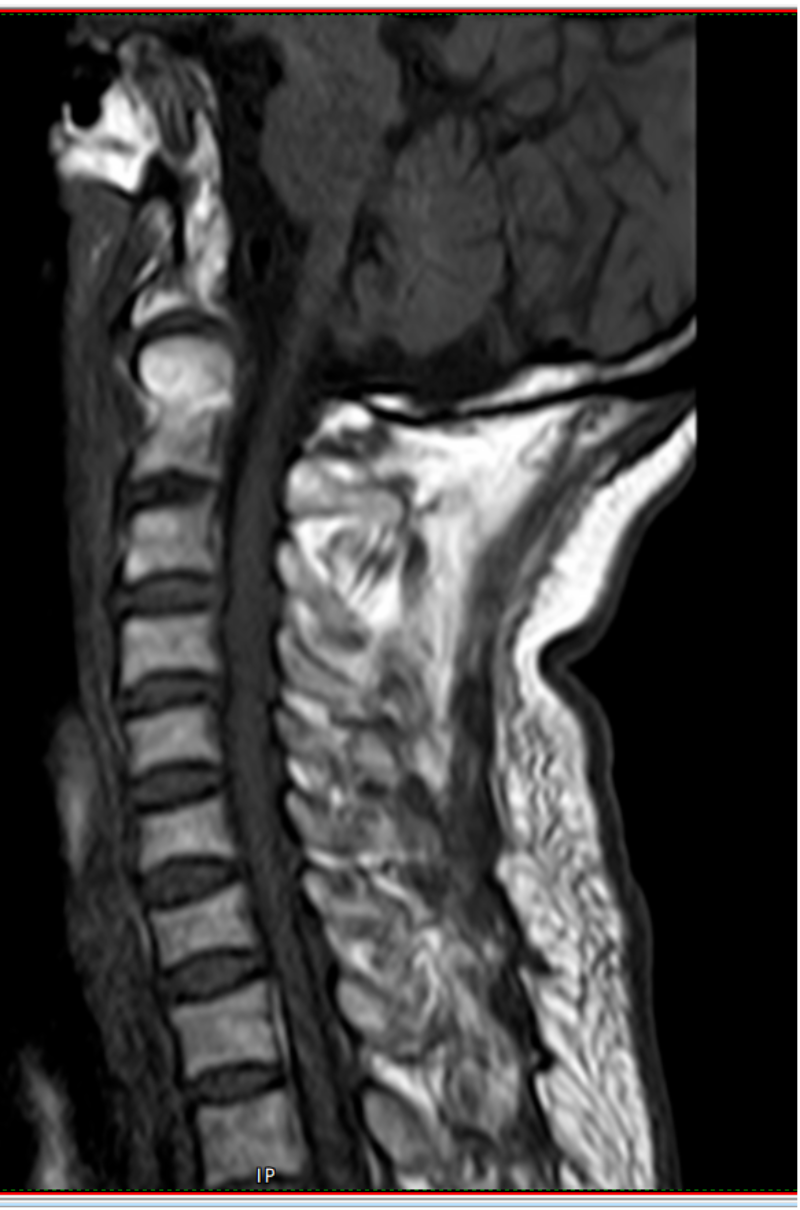

73歲的黃先生因不慎摔倒從山坡上滾下頭面部先著地致“寰椎骨折”入住惠州市中心人民醫(yī)院博羅分院(博羅縣人民醫(yī)院)脊柱外科。入院時(shí)患者頸肩部、雙上臂疼痛劇烈,伴有雙上肢麻木感,活動(dòng)受限。

術(shù)前檢查

初期給予黃先生頸托外固定保守治療,但考慮頸托限制活動(dòng)不穩(wěn)定,容易松動(dòng),上頸椎解剖位置關(guān)系特殊,位置重要,且鄰近解剖關(guān)系復(fù)雜,病變引起的臨床癥狀嚴(yán)重、多變及輕重不一,愈合率低,其中老年患者保守治療的死亡率高達(dá)21%-33.3%,是年輕患者的21倍,而該骨折手術(shù)風(fēng)險(xiǎn)大、技術(shù)難度高,患者及家屬對(duì)手術(shù)心存顧慮。面對(duì)此困境,姚仕奮主任憑借豐富的臨床經(jīng)驗(yàn),深入分析了患者的病情及身體狀況,經(jīng)過多次科室討論,建議黃先生進(jìn)行寰椎骨折閉合復(fù)位halo架外固定術(shù)治療,halo架無需手術(shù),避免上頸椎手術(shù)的高風(fēng)險(xiǎn),且能提供穩(wěn)定的頸椎外固定,治療效果確切,并且避免患者長期臥床而導(dǎo)致各種并發(fā)癥。

姚仕奮表示,黃先生的寰椎骨折屬于高位頸椎損傷,不幸中的萬幸是受傷后頸椎骨折后釋放了大部分暴力,雖然寰椎前弓粉碎性骨折比較嚴(yán)重,但頸椎脊髓反而受傷較輕,經(jīng)過及時(shí)恰當(dāng)治療,預(yù)后恢復(fù)良好。因此,他提醒,廣大市民們要引起高度重視,對(duì)于脊柱骨折脊髓損傷患者應(yīng)及時(shí)就近診治,特別是頸椎受傷后肢體麻木乏力者不要隨意移動(dòng),需及時(shí)送到有脊柱外科專業(yè)團(tuán)隊(duì)的醫(yī)院救治,曾出現(xiàn)過病人傷后不恰當(dāng)搬運(yùn)及轉(zhuǎn)運(yùn)而出現(xiàn)癥狀加重的情況,甚是可惜。